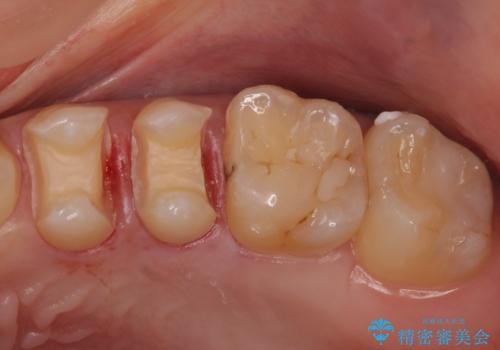

- 銀の詰め物を白くしたいとのことで来院。

銀の詰め物を除去した後、う蝕が残っていないかを拡大鏡下で確認し

セラミックの詰め物(e-maxインレー)にて治療を行いました。